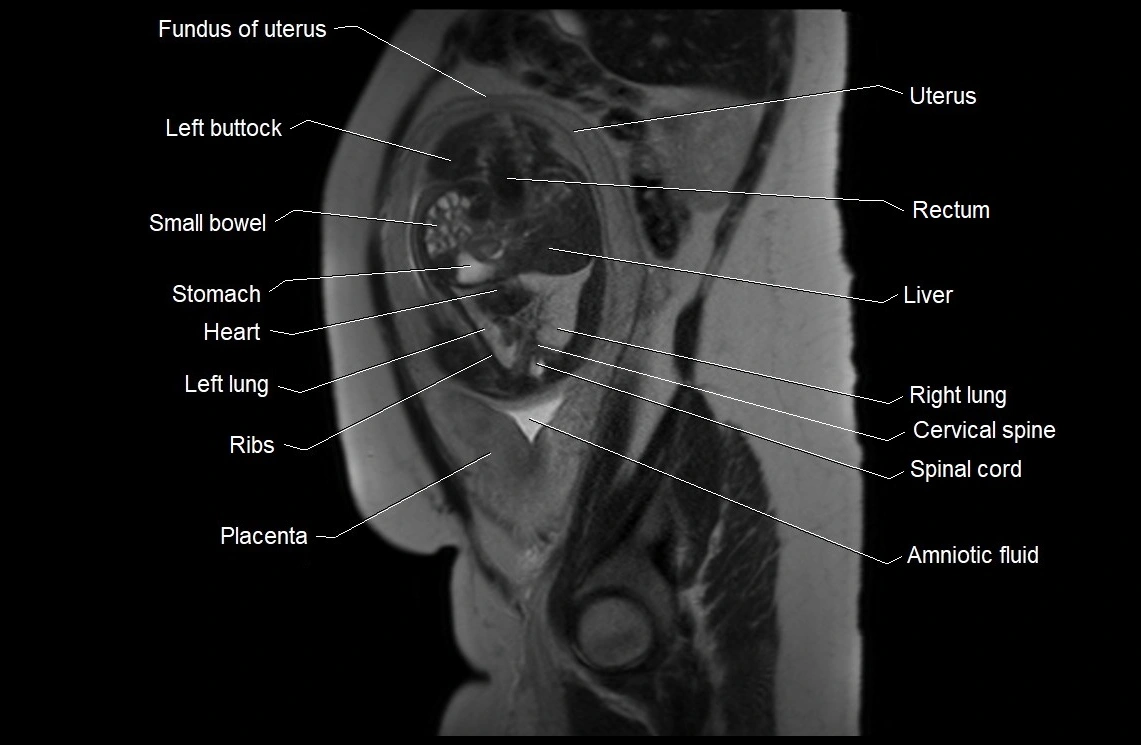

MRI Appearance

T2 HASTE (T2 GRE):

• Amniotic fluid shows very bright hyperintense signal

• Provides natural contrast against fetus and placenta

• Small particles (vernix) may appear as scattered hypointense foci within bright fluid

T1 GRE:

• Amniotic fluid shows low signal intensity (dark)

• Hemorrhage, infection, or proteinaceous content may cause focal or diffuse high signal intensity

MRI image

image